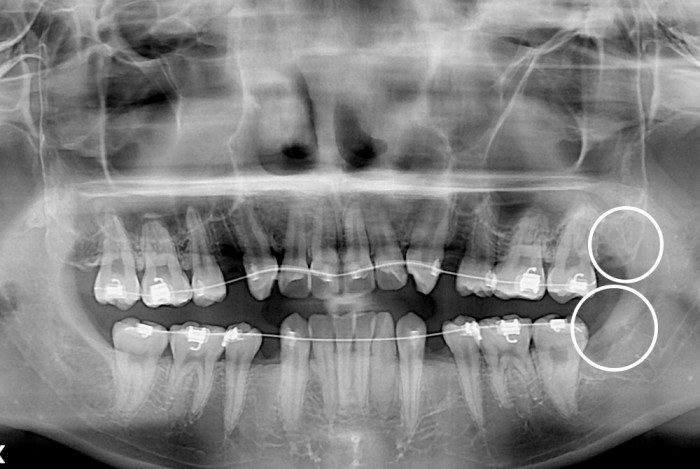

[사랑니] 사랑니

치료후 : 2019-06-21

세종치과는 구강악안면외과학 박사이신 원장님이 발치하는 치과입니다.